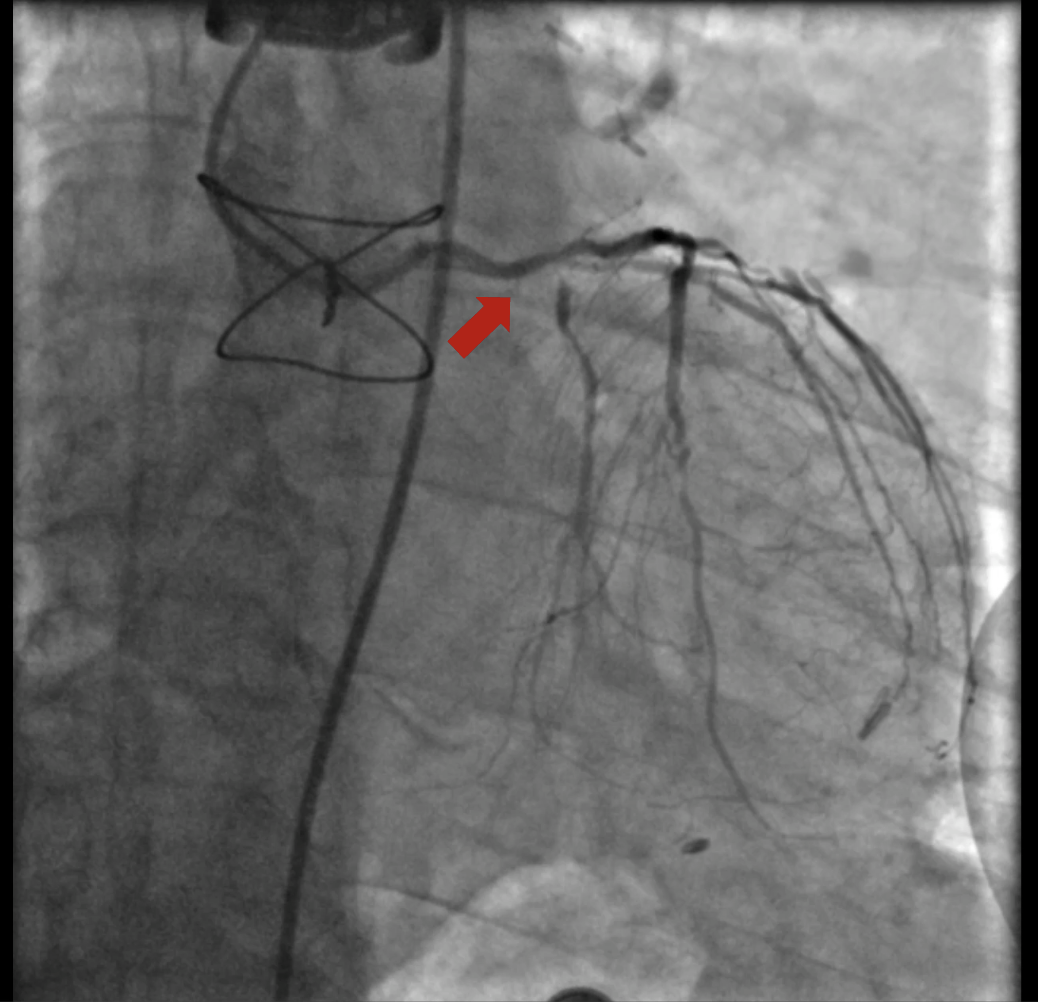

At the first encounter, coronary angiography revealed a left main bifurcation lesion (Medina 1-1-1) with 99% ostial stenosis of the LCX and severe stenosis in the proximal LAD and the 2nd diagonal branch. Collateral circulation was observed from the LAD and LCX to the distal RCA. Right coronary angiography showed a proximal CTO with a J-CTO score of 3 due to calcification, bending, and lesion length. The LIMA was not grafted to the LAD.

At the 1st encounter, RCA CTO PCI was performed with a plan for staged PCI of the left system. Using a 7F AL 0.75 for strong support, an antegrade approach with a double-lumen microcatheter and parallel wire technique (Pilot 150) successfully crossed the lesion. Predilatation with a 1.5 ¡¿ 15 mm balloon was done. IVUS could not pass due to 360¡Æ calcification. Rotablation with a 1.25 mm burr was attempted but limited to mid-RCA. Two DES were implanted from mid to proximal RCA, followed by post-dilatation.At the 2nd encounter, RCA stents were patent. PCI was done on LM, LAD, and D2. D2 was treated with DCB. LAD predilatation followed by OCT showed severe 330¡Æ calcification (max thickness 1.04 mm, MLA 1.63 mm©÷). IVL with a 2.75 ¡¿ 12 mm balloon (30 pulses) achieved multiple calcium fractures. A 2.75 ¡¿ 33 mm DES was deployed with good OCT results.At the 3rd encounter, 6 months later, the patient presented with ADHF. Angiography revealed RCA ISR CTO at the mid-bending site. The lesion was crossed with a Pilot 200 wire; predilatation showed a dog-bone sign. We do balloon based strategy for plaque modification using cutting, scoring, and double-wire balloons. IVUS showed stent underexpansion with 270¡Æ calcification and distal RCA stenosis. IVL with 2.5 and 2.75 mm balloons optimized the lesion, followed by two DES from distal to mid RCA. Post-PCI IVUS confirmed good result.